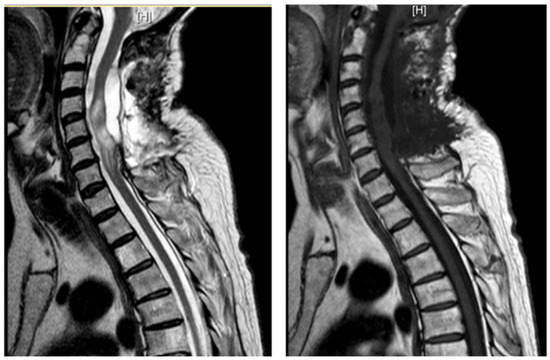

3.4.2. Case 2

| Level | T12–L2 | C5–C6 | T7–T10 | T8–T9 | T8–T11 |

| Location | Intramedullary | Intradural | Intradural–Extradural | Intramedullary | Intradural |

| Primary/secondary | Secondary | Secondary | Secondary | Secondary | Secondary |

| Surgical treatment | lysis of adherences and syrinx cavity opening | resection of the cystic formation and adhesiolysis | resection of the cystic formation and adhesiolysis | resection of the cystic formation and adhesiolysis | resection of the cystic formation and adhesiolysis |

| Complications | CSF fistula | infection | None | CSF fistula | None |

| KPS pre-op (%) | 70 | 50 | 70 | 80 | 90 |

| KPS post-op (%) | 80 | 50 | 60 | 90 | 80 |

| ASIA score pre-op | C | B | B | C | D |

| ASIA score post-op | D | B | C | C | D |